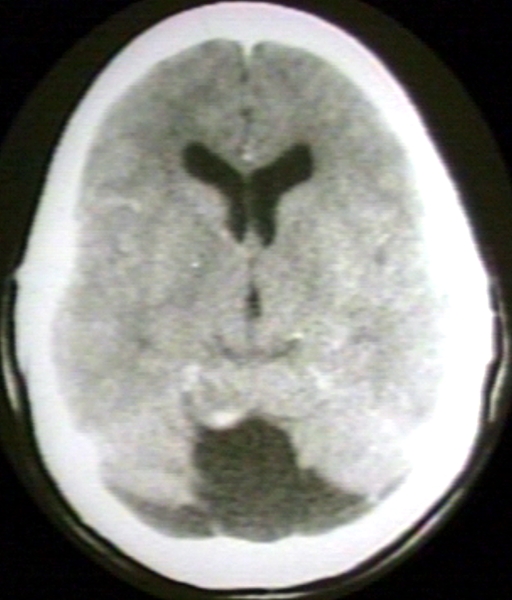

RADIOLOGY: NERVOUS: BRAIN: HEMANGIOBLASTOMA, CEREBELLUM; CYSTIC, HETEROGENEOUS, CALCIFICATION (CT)